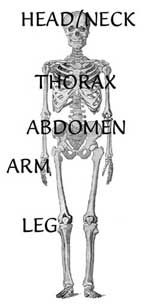

The Visible Human Project sometimes overwhelms new students with the amount of marterial available and how it is displayed. This site is an excellent introduction to what is available in the project with a large number of images. The explanation of planes of sectioning is excellent as are the wonderful animations that accompany each. The Interactive Annotations section has several sections that have annotations that are selected by clicking on the actual Visible Human images. It is an excellent example of how these images can be used educationally.